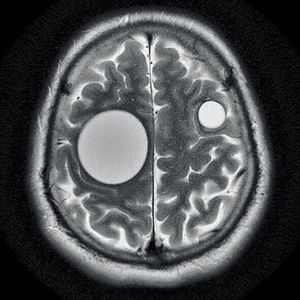

This unique image shows perfectly round hydatid cysts within the brain of a 35-year-old male previously treated for a liver infection. The common cause is a parasitic infection by Echinococcus granulosus. The infection is acquired via contaminated food with eggs of the tapeworm. The oncospheres released from the eggs in the bowel enters the portal circulation. Hence the liver is most commonly affected, followed by the lung and other organs such as bones, genitourinary system, bowel and subcutaneous tissues.Hydatid cysts end up in the brain due to direct invasion of larva that managed and filtered via liver and lung to the brain. The MRI shows well-defined circumscribed spherical non-enhancing intra-axial cystic lesion that usually lies in the territory of the middle cerebral artery.Management is surgical, with removal of the entire cyst without rupture using Dowling’s maneuver (instilling warm saline between the cyst wall and the brain).Credit to @radiopaedia